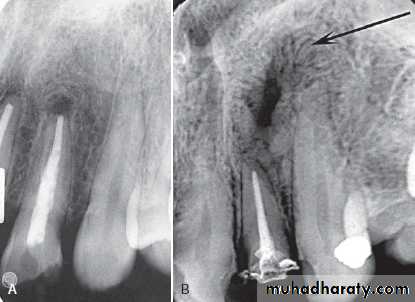

Osteoradionecrosis of the maxilla. (A) before radiotherapy and (B) within 6 months of receiving the radiation. Note the combination of bone sclerosis, bone destruction around the teeth and alveolar crest and widening of the periodontal membrane space.

B

A